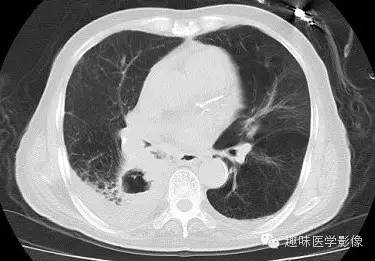

【病例】肺脓肿1例CT影像特点

[影像描述]

双肺多发无壁低密度区,以右肺下叶底部为主。右肺下叶见大片不规则实变阴影伴多发空洞影,实变肺组织内见支气管气象,右肺下叶支气管局部显示不清。纵隔内见淋巴结。右侧胸腔内见积液影,邻近胸膜肥厚。主动脉、冠状动脉钙化。

右肺下叶肺脓肿、肺炎伴胸腔积液,肺气肿、肺大泡。

右胸廓变小,心影右移;右肺下叶多房性空洞,空洞内未见明显液平面,右下肺病变应该是下叶阻塞性肺炎,实变肺组织内见支气管气像,邻近胸膜增厚,并合并胸腔积液,支持肺脓肿。